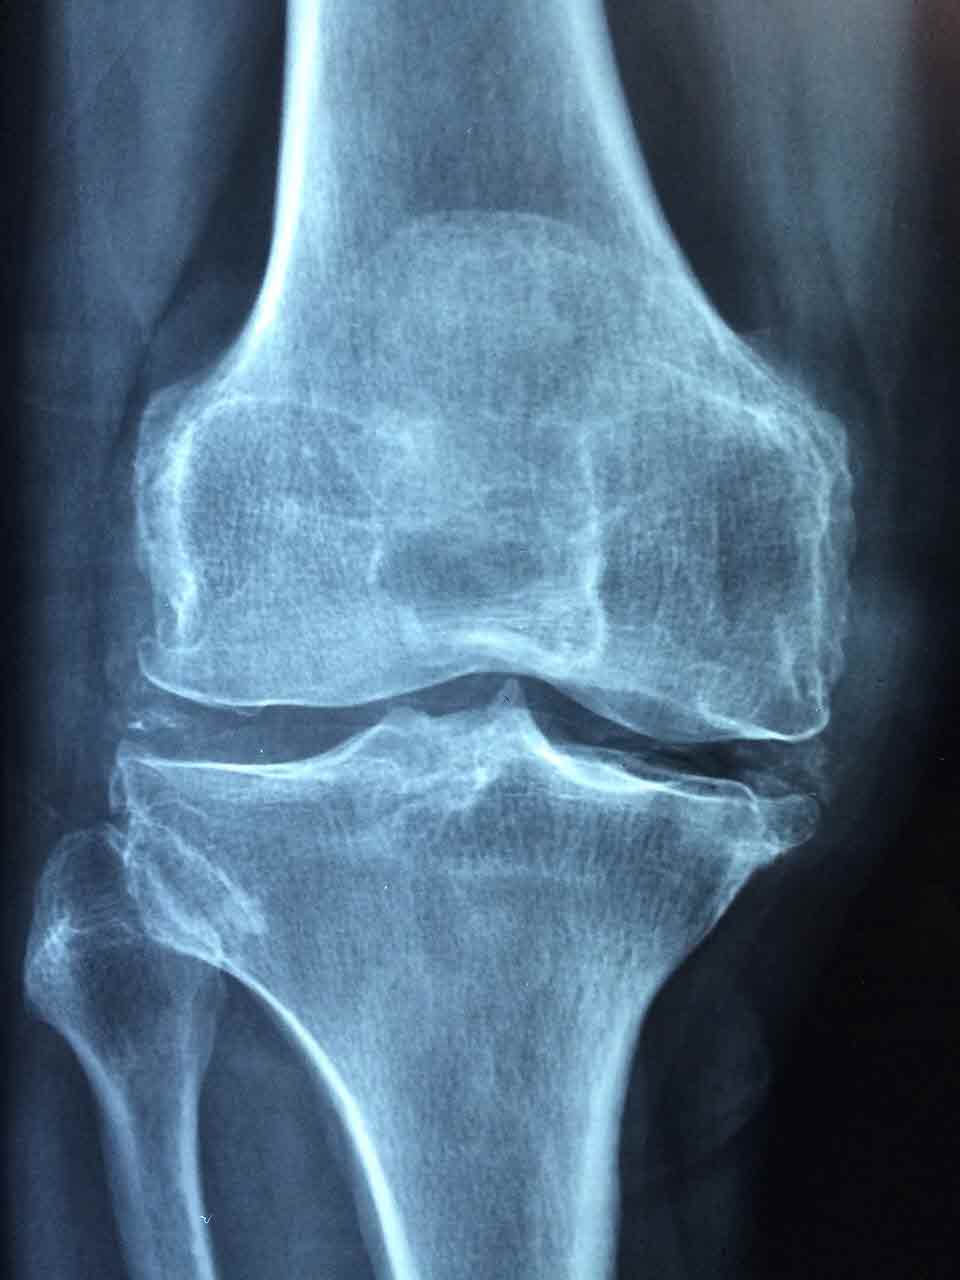

골밀도 측정은 뼈 건강 상태를 알 수 있는 가장 정확한 방법으로,

일반적으로 허리, 엉덩이 부위 X선 촬영으로 검사합니다.